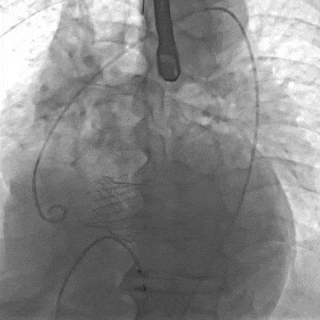

截止目前,临床试验进展顺利,入组已接近尾声。中期分析显示手术成功率和安全性指标均符合预期标准。

瓣膜功能、形态良好,未见反流